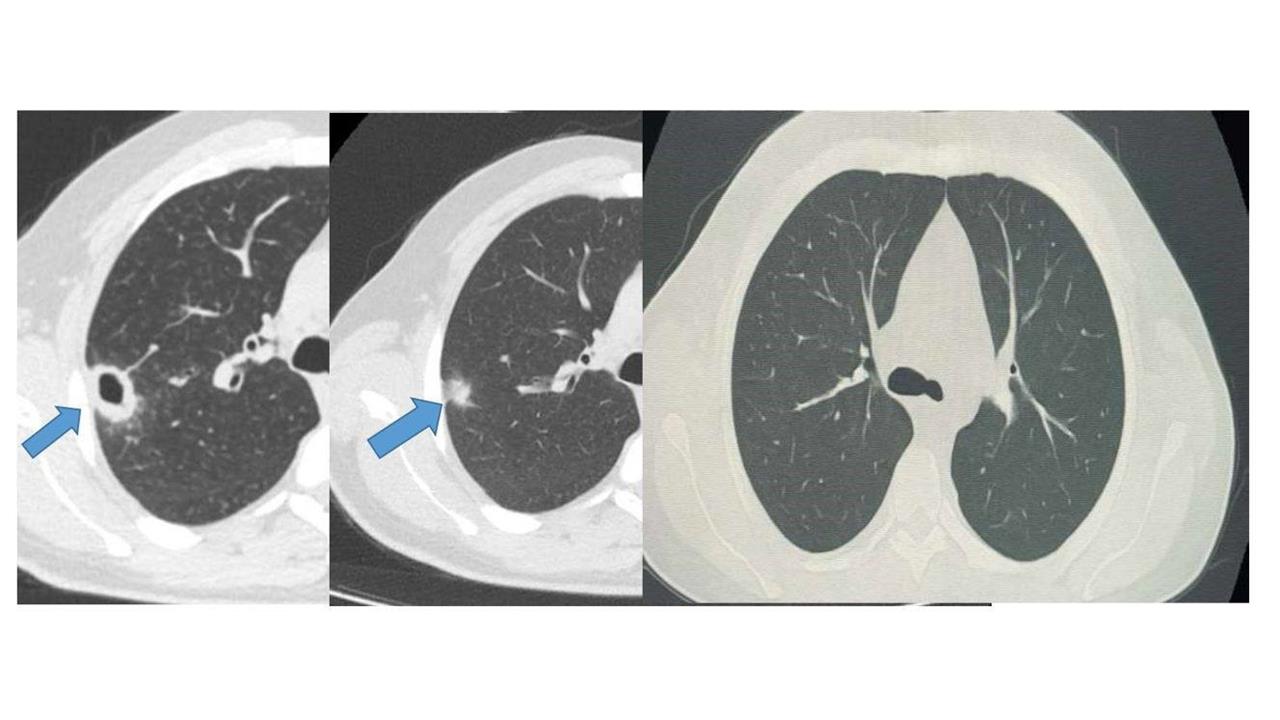

Hastanın muayenesini gerçekleştiren Göğüs Hastalıkları Uzmanı Uzm. Dr. Hilal Sayma, ileri tetkik amacıyla bronkoskopi işlemi uyguladı. Bronkoskopi sonucunda tespit edilen lezyonun kanser veya tüberküloz gibi ciddi hastalıklarla ilişkili olmadığı belirlendi. Bu aşamadan sonra hasta için uygun tedavi süreci başlatıldı.

İki haftalık tedavi sürecinin ardından yapılan kontrollerde lezyonun neredeyse tamamen gerilediği görüldü. Sonuç olarak sağlığına kavuşan hasta taburcu edildi ve durumunun iyi olduğu belirtildi. Bu örnek, erken tanının ne denli önemli olduğunu bir kez daha gözler önüne serdi.